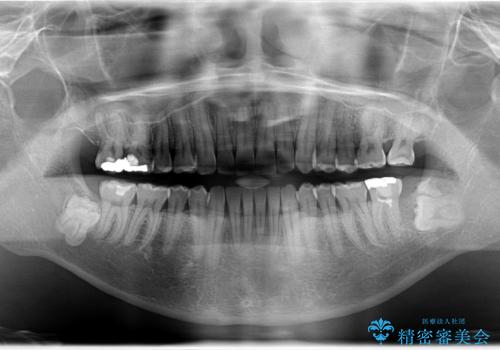

インビザライン invisalign ガタつきを治すマウスピース矯正

- invisalign full

- 非抜歯・上顎臼歯遠心移動によるマウスピース矯正を計画した。

ガタつきを取り除くだけであれば非常に簡潔であるマウスピース矯正ですが、奥歯の位置関係の是正や、垂直的な歯の位置のコントロールなどが計画に含まれる場合、治療が難しくなってきます。